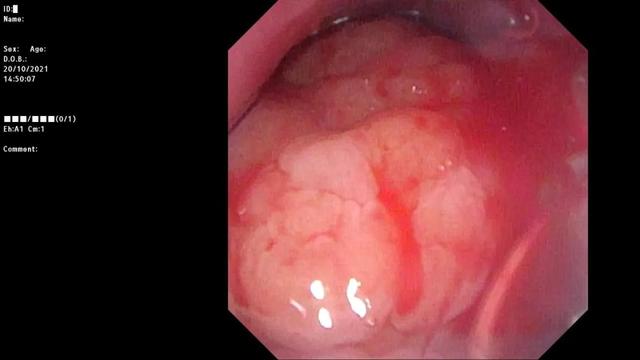

睡眠监测发现,肖鑫确实有阻塞性睡眠呼吸暂停低通气综合征,和低氧血症,陪同,而肖鑫因张力过低在鼻咽镜下显示软腭抬举不良。

腺样体和扁桃体肥大阻塞气道90%以上,软腭提升不良,意味着肖鑫气道受到多重压迫。

腺样体堵塞后鼻孔近100%。